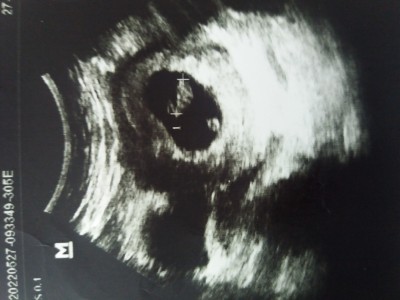

8 haftalıkken gitmiştim  bebeğin aşağısındaki  bir bebek dahamı var demekten alıkoyamıyorum kendimi;)3 tane gebelik yaşadım böyle hic dikkatimi çekmemişti resimlerde.6.haftadaysa beta 15000.00 çıkmıştı ondanda şüphelenmiştim.ikiz olsa kalp atışı falan görülür  diye düşünüyorum sizce nedir kızlar o???image

Yolk sac o Canım ilk o oluşur sonra bebeğin google dan araştır istersen detaylı bilgi var

Yolk o bndede iki tane var ne diye sordum doktoruma o yolk dedi bebek ondan besleniyor dedi